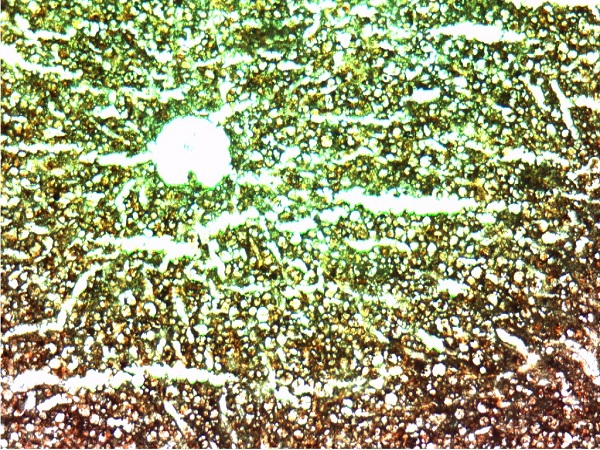

肝淀粉样变2(淀粉染色10X10)